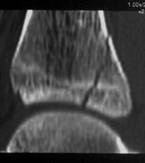

S-HⅡ S-HⅢ

S-HⅢ

S-HⅣ